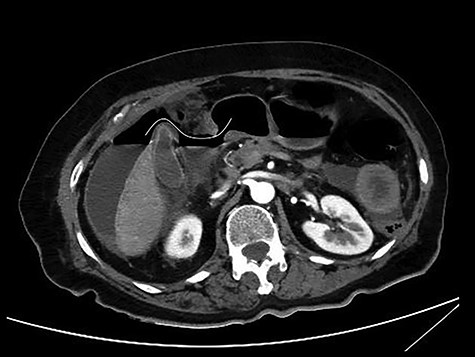

CT multiplanar reconstruction (upper level, supine position) shows free air in continuity with intraluminal (duodenum) air. Notice the presence of free fluid in mesenteric pouches (stars), as well as encapsulated in the right paracolic gutter (arrows) and Douglas space (long arrow).

Subsequently, an emergent exploratory laparotomy was decided upon. The exploration of the peritoneal cavity revealed a large amount of dirty fluid, total absence of the anterior and lateral walls of the first part of the duodenum and total bowel discontinuation after the pylorus (Fig. 4). No other disorder or sign of metastasis was present. The pylorus was sutured, a transmesocolic gastroileac anastomosis was performed and a Pezzer tube was placed in the duodenal remnant. Three drains, in Douglas, and in the right and left space were also placed. Empirical triple antibiotic treatment was administered. Postoperatively, the patient remained in the intensive care unit for 24 h. Her hospital stay was further complicated with wound dehiscence and spontaneous low-output enterocutaneous fistula, which were treated conservatively. The patient was discharged in good health on the 28th postoperative day, and the Pezzer tube was safely removed 1 week later.